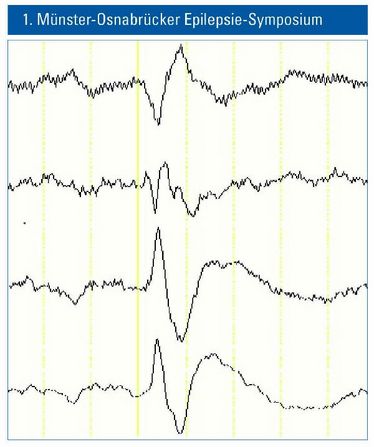

1. Münster-Osnabrücker Epilepsie-Symposium

1. Münster-Osnabrücker Epilepsie-Symposium